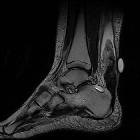

MRI

Appearances can vary:

- a full-thickness tear often shows a tendinous gap filled with edema or blood

- complete rupture shows retraction of tendon ends

- T2: partial thickness or interstitial tears may show high signal on long TR, and tendon swelling to >7 mm AP